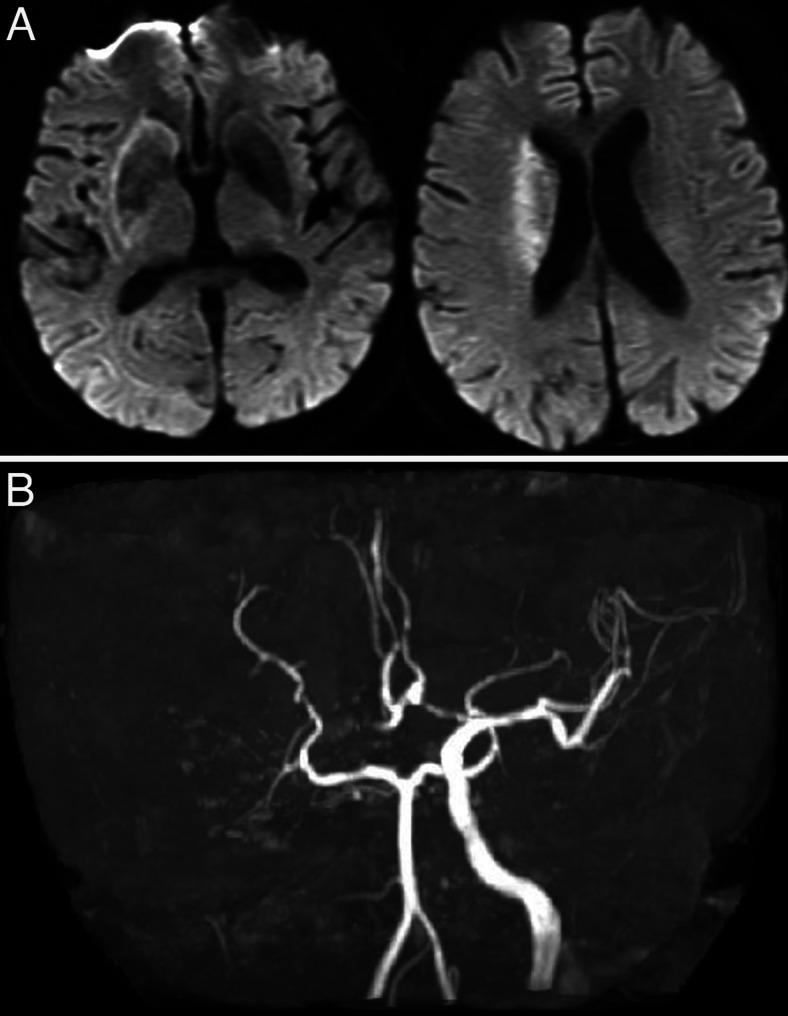

OBSERVATIONS

A 73-year-old man was emergently brought to the authors' hospital because of left hemiparesis and consciousness disturbance. An ischemic lesion of the right cerebral hemisphere and the right internal carotid artery occlusion was revealed. Emergently, endovascular treatment was performed, and occlusion of the artery was reanalyzed. However, he suffered from hypotension with electrocardiogram abnormality. Subsequently, coronary angiography was performed, but the arteries were patent. The authors made a diagnosis of takotsubo cardiomyopathy.

观察结果

一名73岁男性因左侧偏瘫和意识障碍紧急被送至作者所在医院。发现右侧大脑半球存在缺血性病变以及右侧颈内动脉闭塞。紧急进行了血管内治疗,并再次分析动脉闭塞情况。然而,他出现了低血压伴心电图异常。随后进行了冠状动脉造影,但动脉通畅。作者诊断为应激性心肌病。